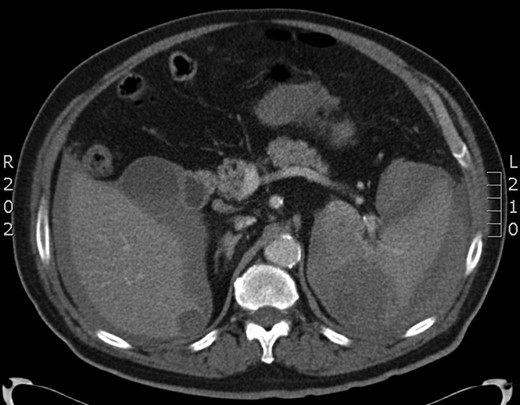

After initial resuscitation with intravenous fluids and starting of empirical antibiotics, an urgent CT scan of his abdomen and pelvis was obtained, which showed an abnormal spleen with signs of rupture and free intraperitoneal blood (Figs 1 and 2). On the basis of these findings, he was taken immediately to theatre after correction of his coagulation with 5 mg of vitamin K and 2000 units of Human Prothrombin Complex (Octaplex).

Coronal section of the CT scan showing the abnormal spleen and the haemoperitoneum.